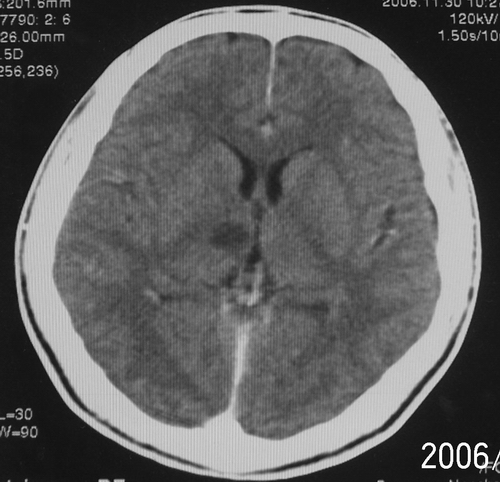

患者、男、18y,头痛5天入院。

左小脑、右丘脑区低密度影,无明显强化及占位表现,男18y,先考虑脑部炎性病变,如脑炎、血行播散性感染等,建议结合临床如脑脊液检验。

单独看左侧小脑半球的不规则形囊性低密度灶,从发病部位、年龄以及无强化、无占位效应的特点可以考虑毛细胞瘤型星形细胞瘤。同样,如果单独看右侧丘脑的近圆形低密度,也可以考虑囊变形星形细胞瘤。只是胶质细胞瘤一般为单发直接浸润、蔓延生长,而不是在脑内同时出现多个病灶,且瘤周没有一点儿水肿,暂时不予以考虑。

左侧小脑半球及右丘脑低密度影,考虑  1、脑梗塞灶. 2、占位性病变,建议作mri检查

左侧小脑半球及右丘脑低密度影,还是在做个mri较为妥当。